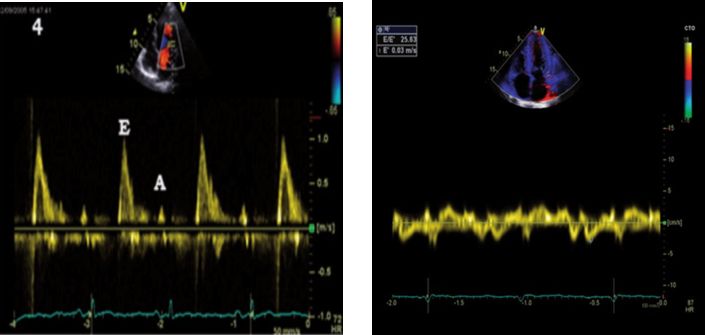

A图:二尖瓣口血流频谱显示为限制充盈异常,高E峰,小A峰,E/A比值>2

B图:二尖瓣组织多普勒(TDI)显示左室E’=3cm/s,E/E’=25.63(正常人E’>8cm/s)